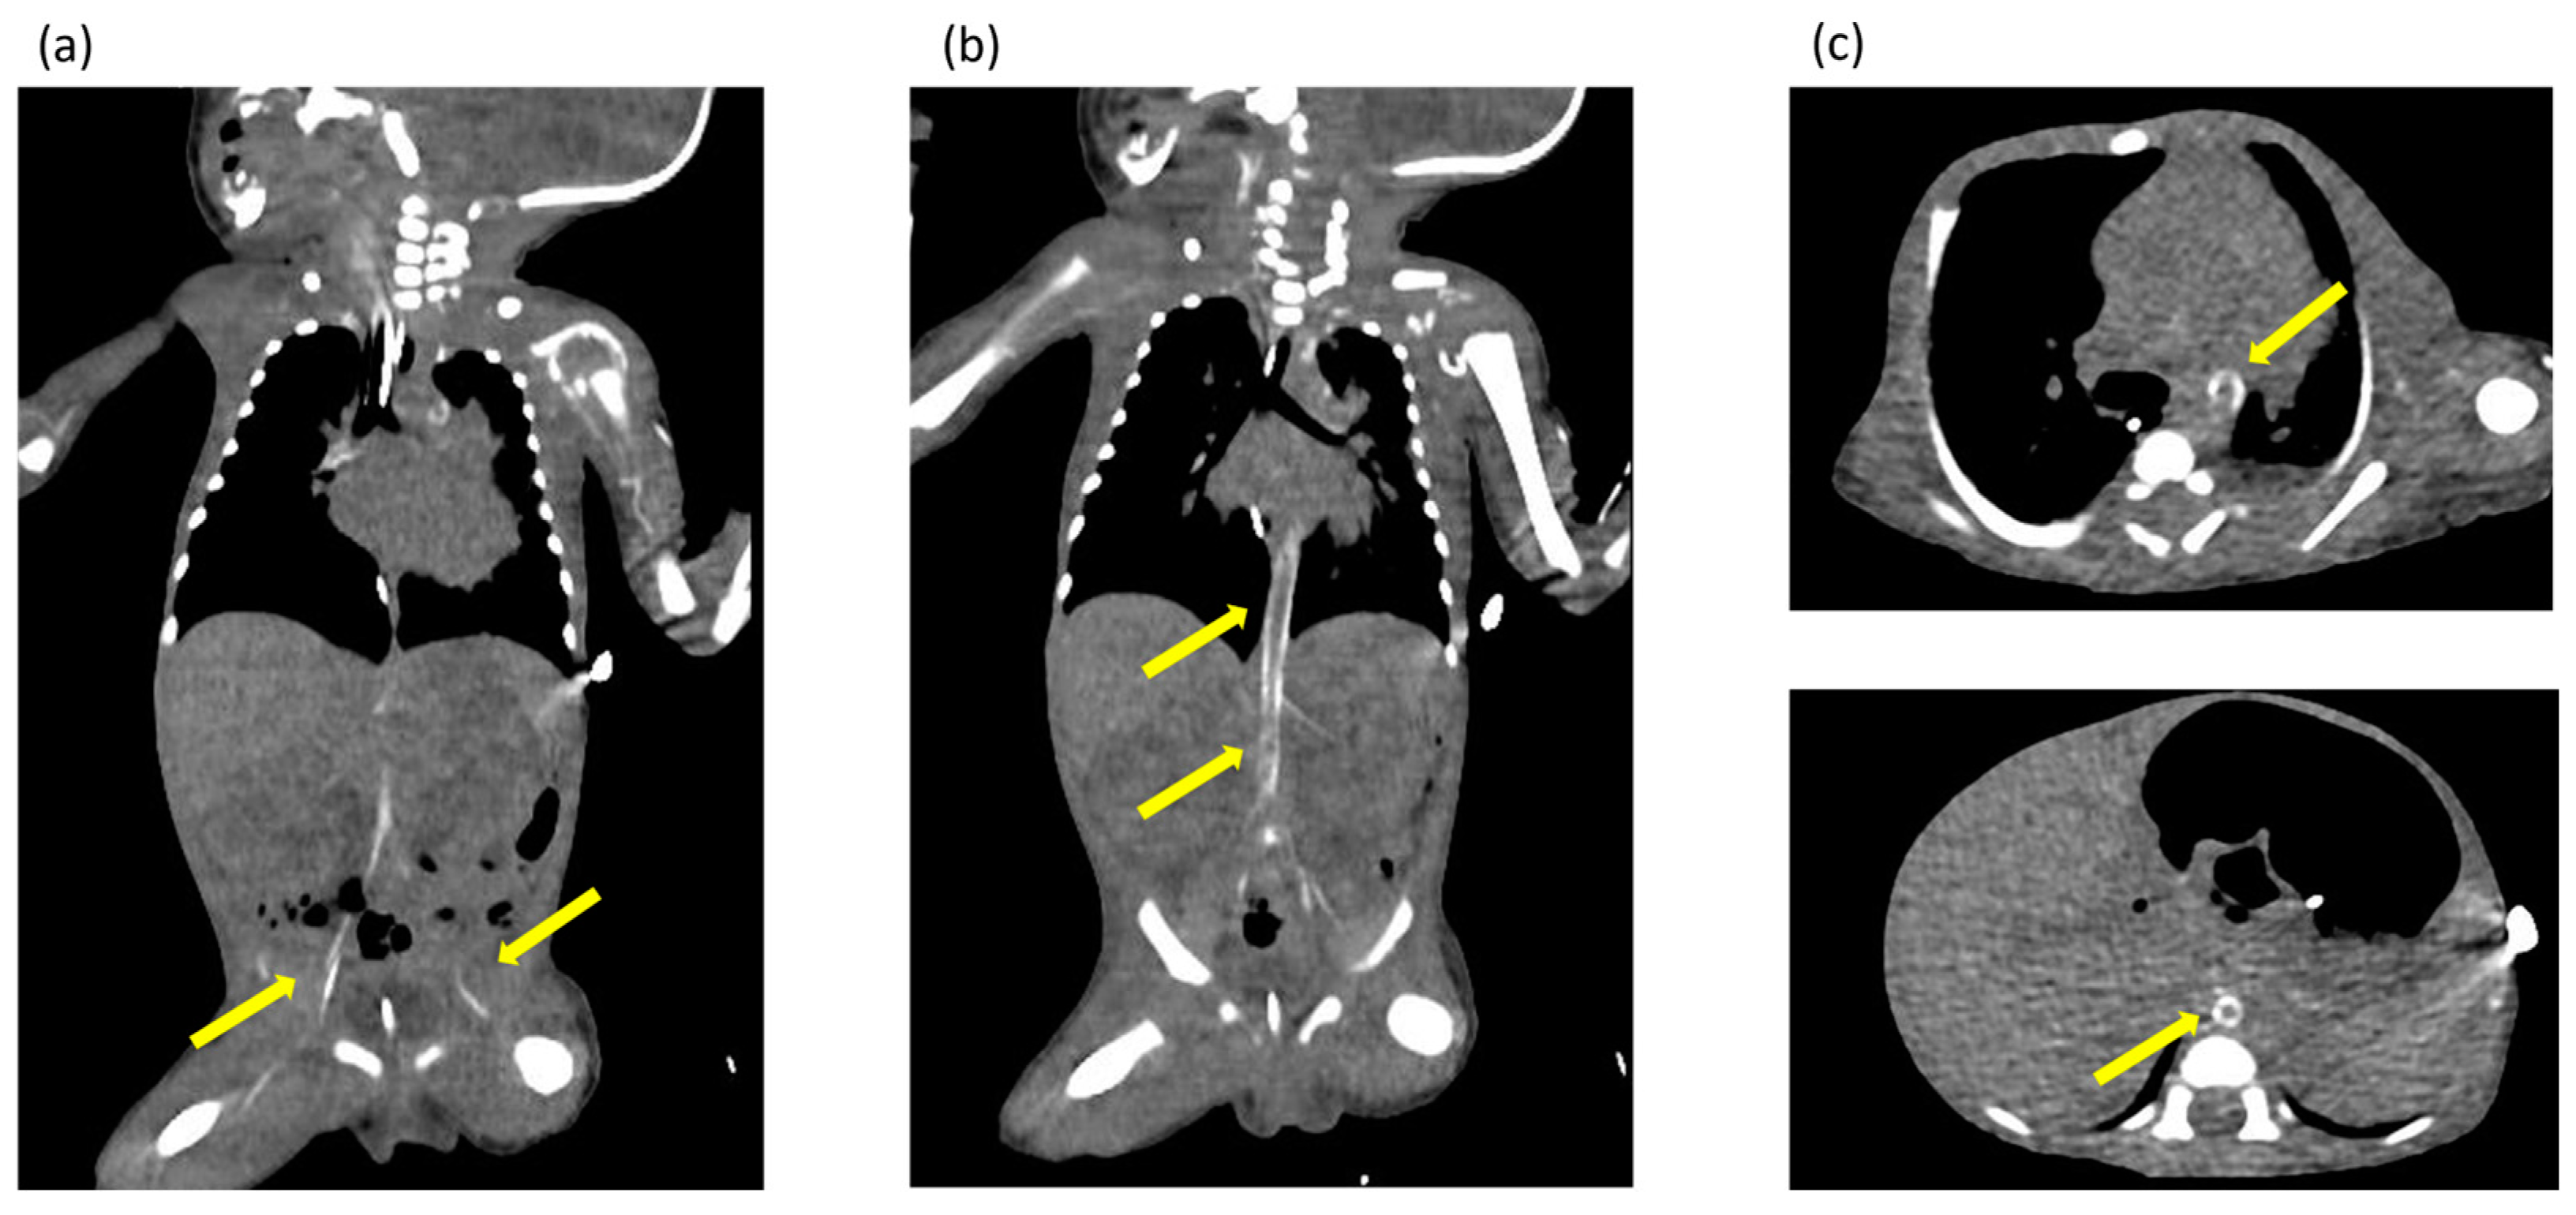

2. Case Presentation